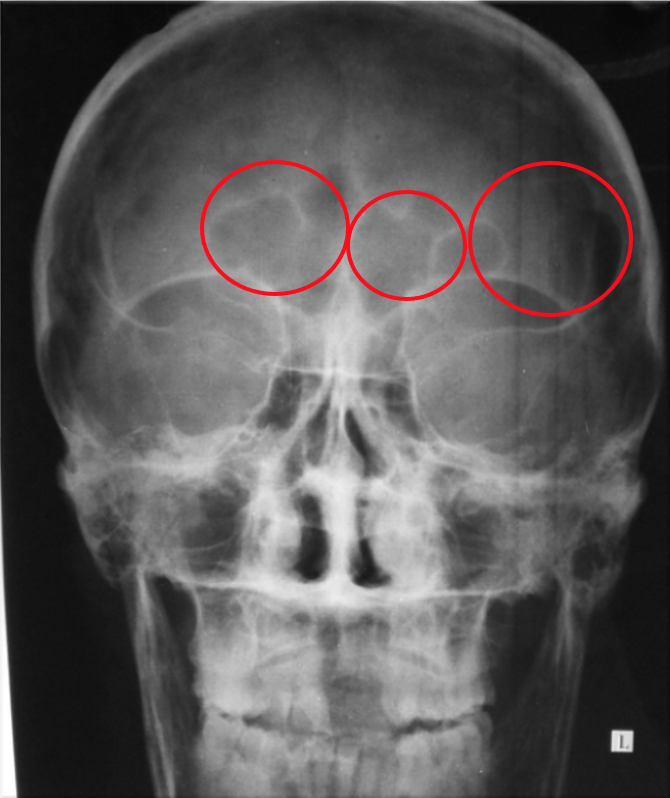

A 76 year old patient presenting with weight loss, tiredness and back pain got their blood tested for a myeloma screen. Blood reports provided from Haematology and Biochemistry showed high calcium and anaemia. X-rays showed bone lesions and a back fracture.

The sample was run for electrophoresis and a monoclonal peak had been detected in the gamma region.